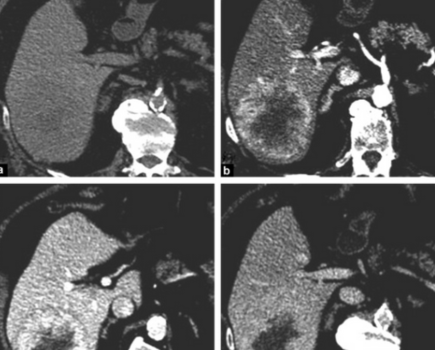

Le système LI-RADS est conçu pour diagnostiquer le carcinome hépatocellulaire (CHC) chez les patients à haut risque, incluant classiquement ceux ayant une cirrhose ou une hépatite virale B chronique. Cette étude sud-coréenne s’intéresse à un sous-groupe bien précis : les patients atteints d’hépatite virale C chronique sans cirrhose.

En analysant rétrospectivement 458 patients (âge moyen : 64 ± 9 ans; 350 hommes ; 219 sans cirrhose, 239 avec cirrhose), les auteurs ont montré que chez les patients sans cirrhose, la catégorie LR-5 avait une AUC de 0,90 (IC95 % : 0,86–0,93), une exactitude (accuracy) de 85,1 % (IC 95 % : 80,6–89,7) et une spécificité de 97,6 % (IC 95 % : 93,0–100,0). Il est d'ailleurs notable que l’AUC pour le diagnostic de CHC les lésions classées LR-5 était significativement plus élevée dans le groupe sans cirrhose que dans celui avec cirrhose (AUC : 0,90 [IC 95 % : 0,86–0,93] vs 0,79 [IC 95 % : 0,74–0,84] ; p = 0,002). La performance diagnostique de la catégorie LR-5 était également excellente dans la cohorte de validation, qui incluait 155 lésions chez 103 patients. Cette étude suggère donc que la performance diagnostique de la catégorie LR-5 pour le diagnostic du CHC chez les patients atteints d’hépatite virale C chronique mais non cirrhotique est similaire à celle observée chez les patients cirrhotiques.